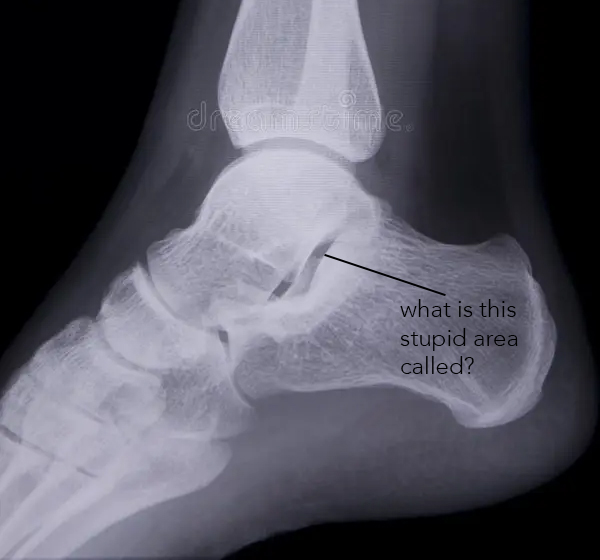

what other joint space is open?

tibiotalar

pic-sustenaculum tali

what joint space is open on a 45° medial rotation ankle besides tibio fibular?

fibulotalar ( is that even a thing? idk, i dont give a fuck)